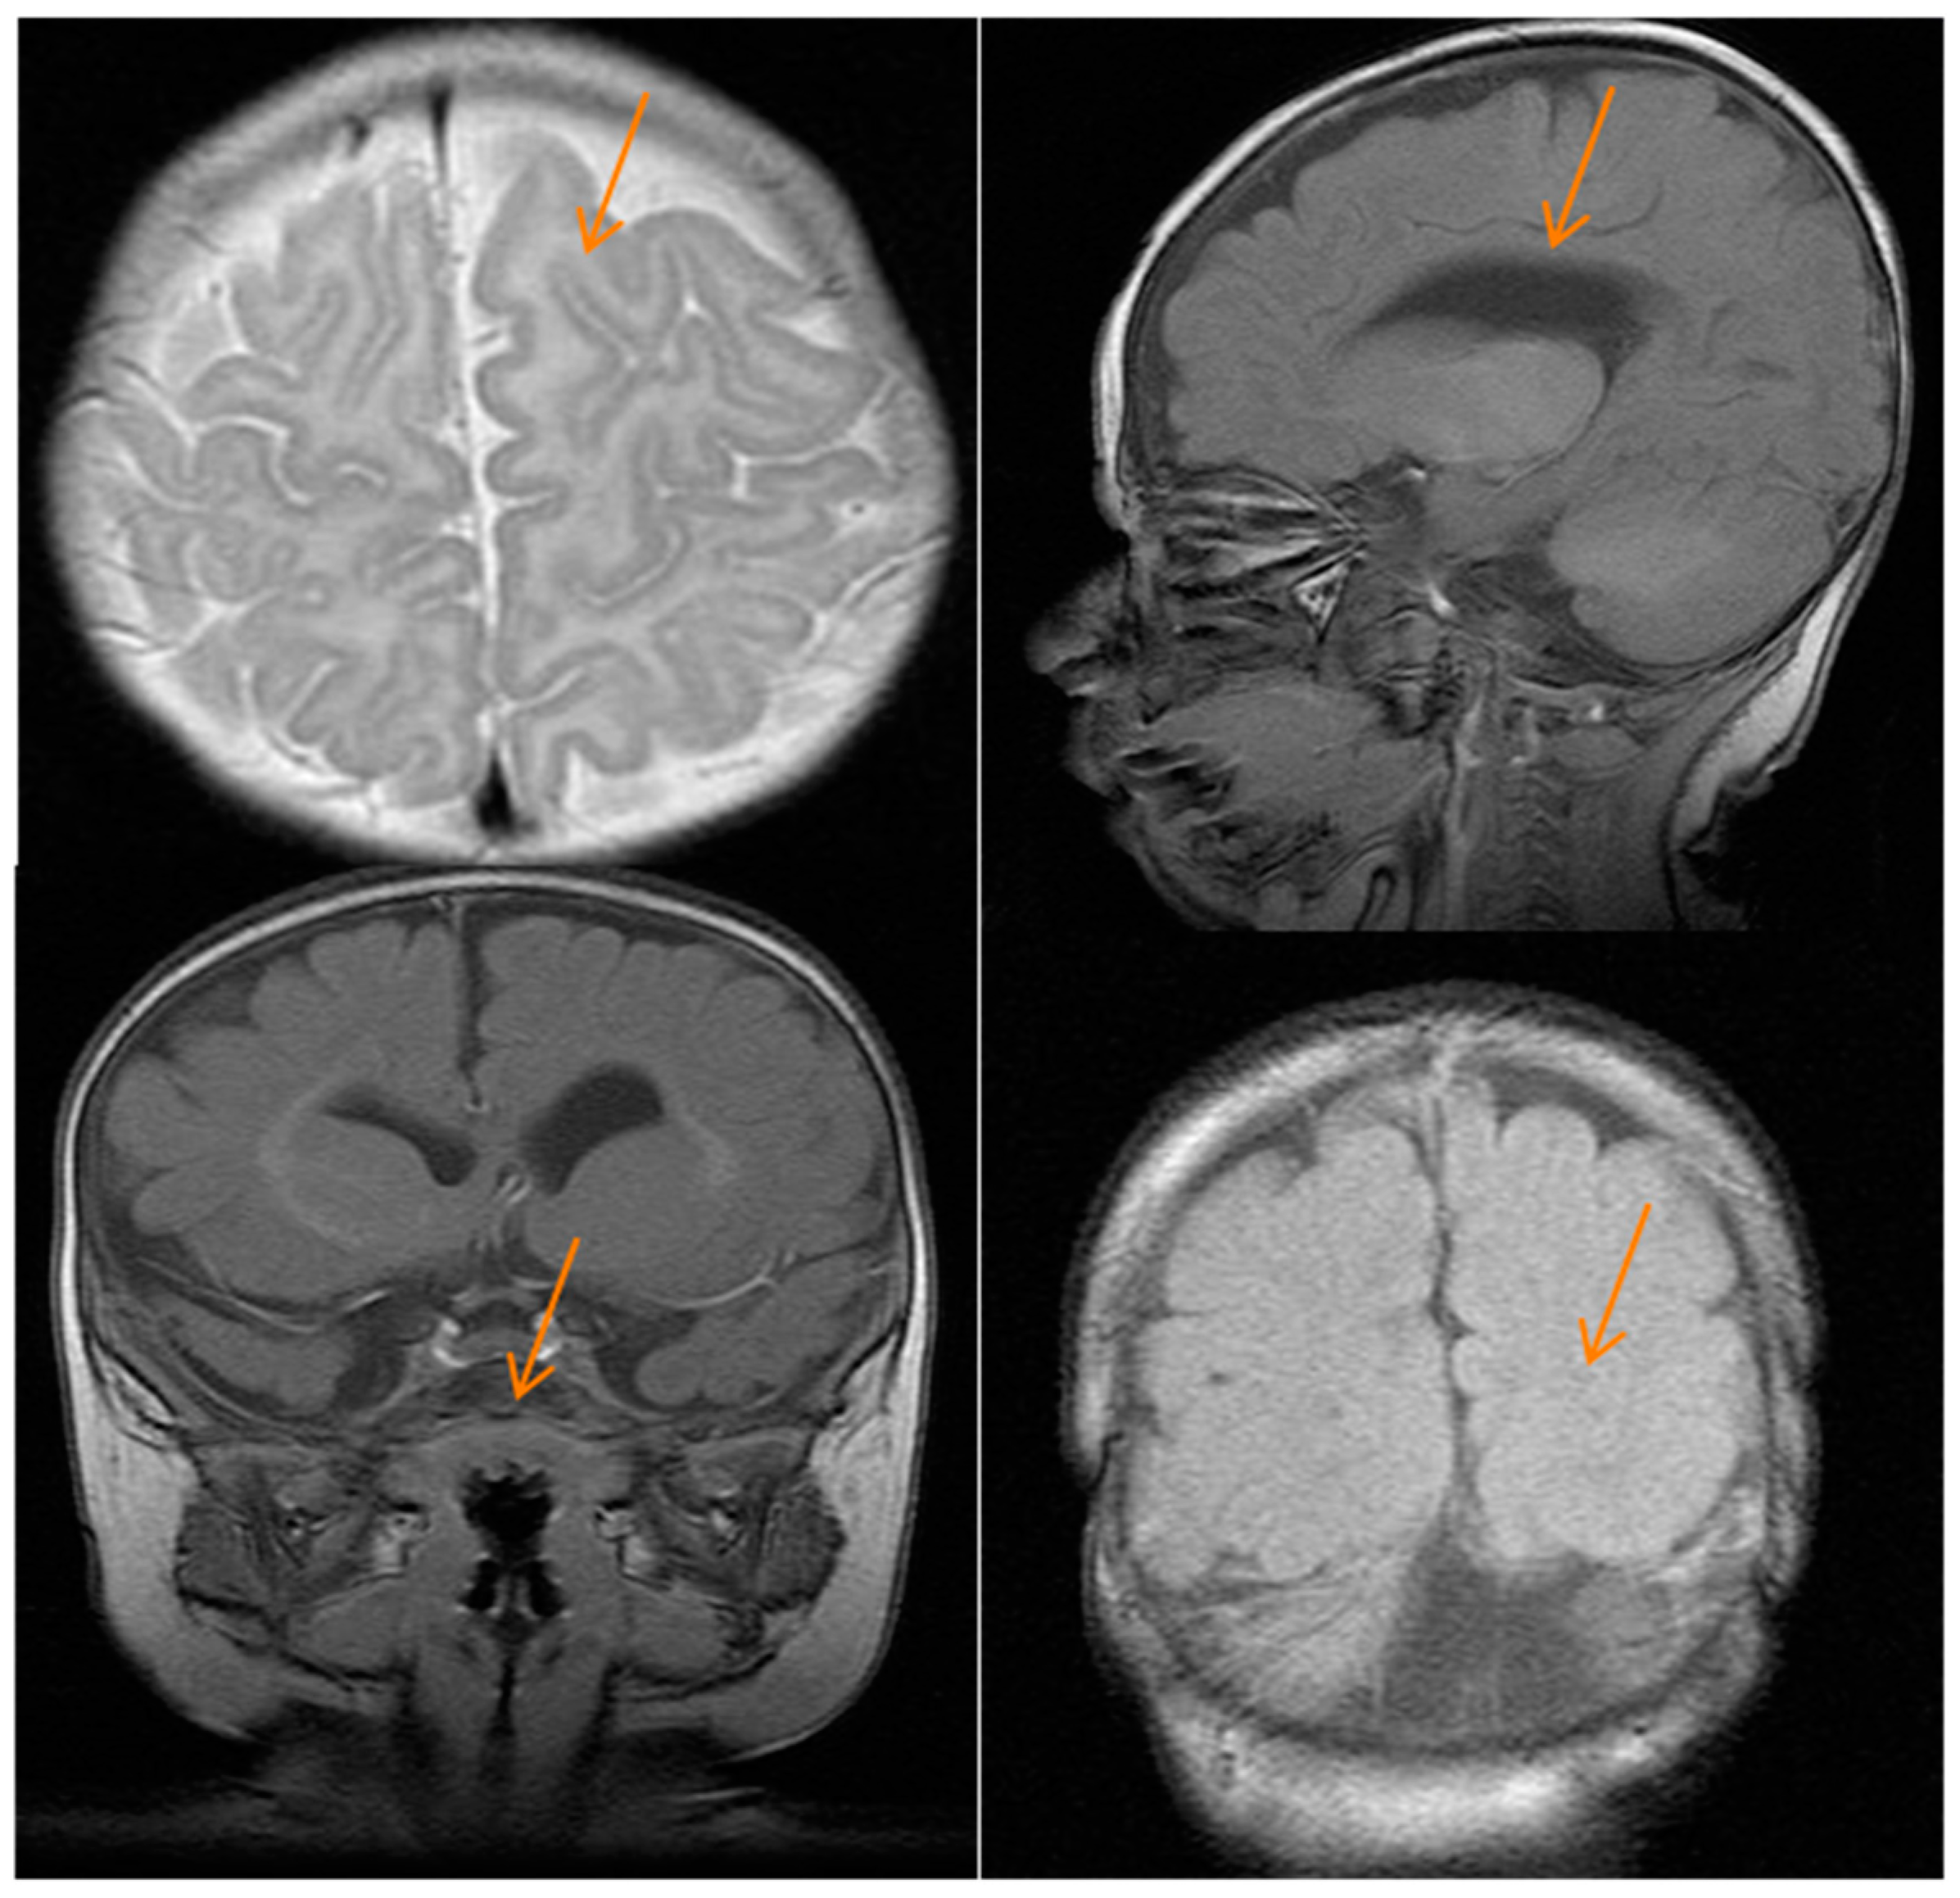

Brain magnetic resonance imaging at four months showed mild asymmetry and dilatation of lateral ventricles (>in right ventricles) with decreased thickness of the white matter of the same cerebral hemisphere and cortical dysgenesis with dysmorphic frontal lobes, a simplified gyral pattern, and poor development of the sylvian fissure. The corpus callosum was thin, and basal ganglia were hypoplastic. The right caudate nucleus and right lentiform nucleus were dysmorphic. Hypoplasia of cerebellar vermis and pons were also seen (Figure 2).

Figure 2.

Brain magnetic resonance imaging of the patient. Images show cortical dysgenesis (top left and lower right figures), a thin corpus callosum (top right figure), and hypoplastic pons (lower left figure); the red arrows indicate the brain defects.